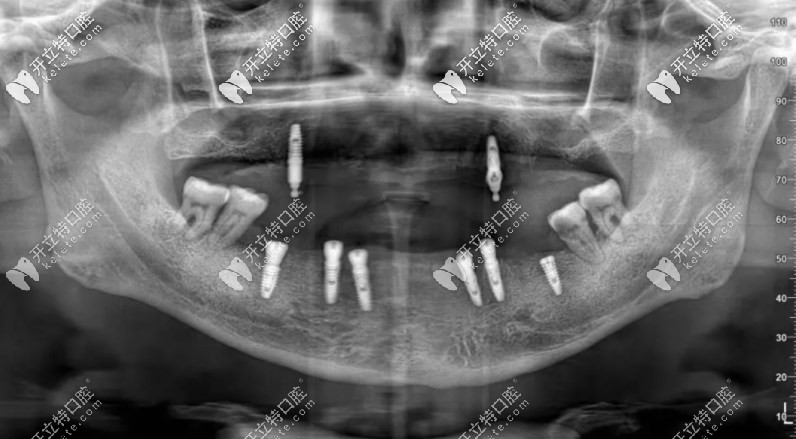

確定是植入了8顆種植體,品牌是德國camlog。

下圖是李叔叔種完牙拍的片子▼